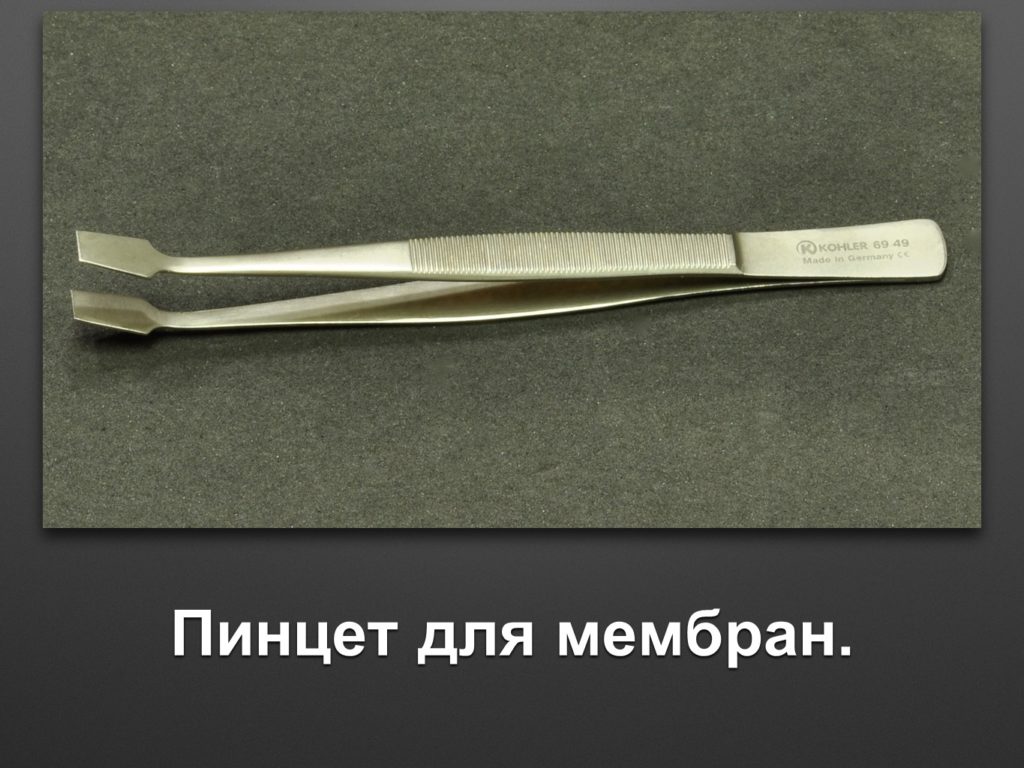

"Выстраданные" наборы инструментов

Все ниже перечисленные инструменты можно приобрести на сайте kohlermed.ru или связаться с нашим менеджером по тел 499-5179401

Все ниже перечисленные инструменты можно приобрести на сайте kohlermed.ru или связаться с нашим менеджером по тел 499-5179401